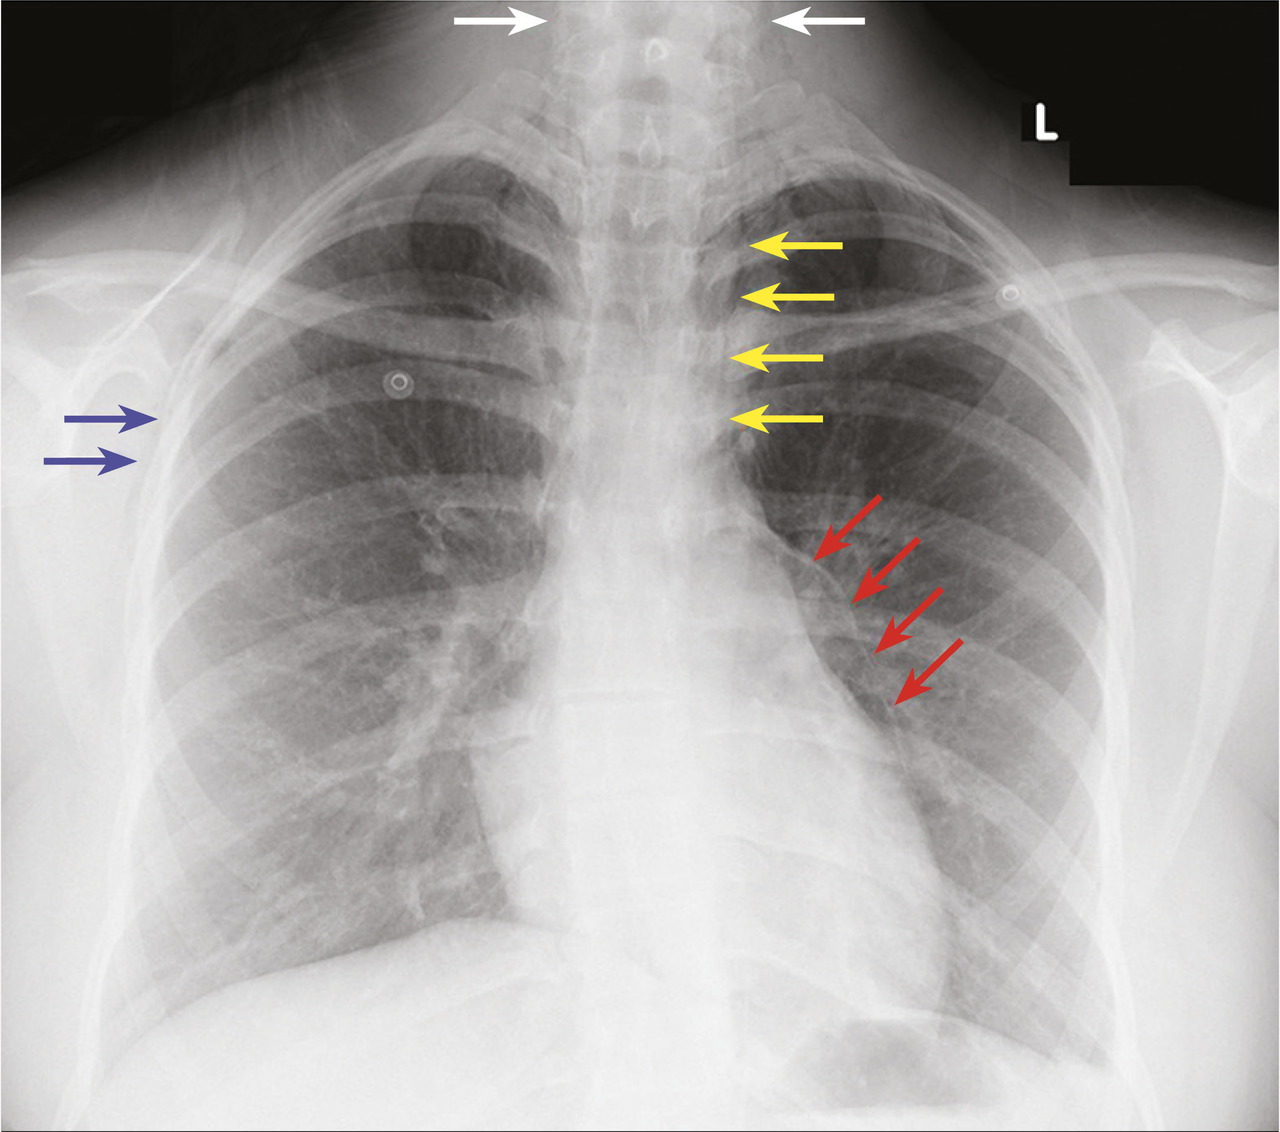

Cette adolescente de 15 ans consultait pour une douleur médiothoracique et cervicale évoluant depuis quelques heures, et une dyspnée sifflante présente depuis 2 jours. Elle avait pour antécédents un eczéma dans la petite enfance et une rhinite allergique. L’examen physique notait des sibilants bilatéraux, une crépitation à la palpation du cou et des creux sus-claviculaires, et une tachycardie régulière avec crépitation rythmée par les bruits du cœur. La saturation en oxygène était à 94 % en air ambiant. La radiographie thoracique (fig. 1) montrait des clartés fines linéaires délimitant le bouton aortique et un emphysème sous-cutané cervico-thoracique, permettant le diagnostic de pneumomédiastin spontané, compliquant une exacerbation d’asthme. Le diagnostic était confirmé par la tomodensi-tométrie(fig. 2). La patiente était surveillée en soins intensifs pendant 72 heures, avec un traitement par corticoïdes systémiques et aérosols de broncho-dilatateurs, puis un traitement de fond par corticostéroïdes inhalés. L’évolution était favorable, avec régression spontanée du pneumomédiastin.

L’exacerbation d’un asthme est la cause la plus fréquente de pneumomédiastin spontané chez l’adolescent,1 par rupture des alvéoles en périphérie des lobules du fait de l’hyperpression intrathoracique. Une douleur brutale, latérothoracique puis médiane, irradiant vers le cou est très évocatrice. L’examen physique montre un emphysème sous-cutané cervical et sus-claviculaire et une crépitation synchrone des bruits du cœur. La radiographie et la tomodensitométrie thoraciques permettent le diagnostic. L’évolution du pneumomédiastin est, en règle générale, spontanément favorable en 72 heures.2